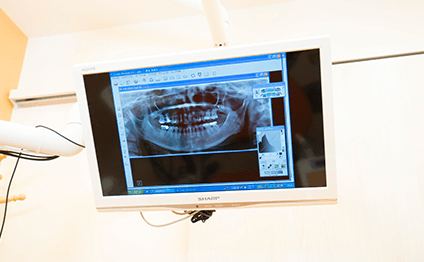

従来のレントゲンに比べ放射線量が1/10とお身体に優しいレントゲンです。

すぐにモニターで見る事ができ、お待たせしません。

レントゲン画像やお口の状態が確認でき、治療計画なども分かりやすく理解する事ができます。